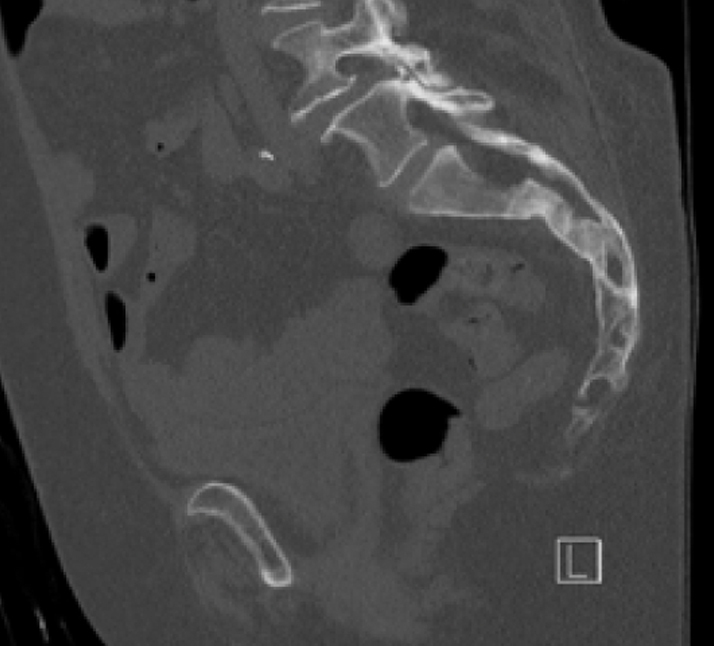

Diagnosis:

• Chronic Sacral U-type fracture with kyphotic deformity

• Anterior ring disruption

• Osteopenia